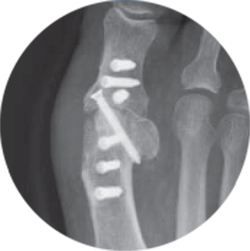

Since the plates are invisible on X-ray, with Barium sulfate added for slight visibility, experience radiolucent artifact-free imaging.